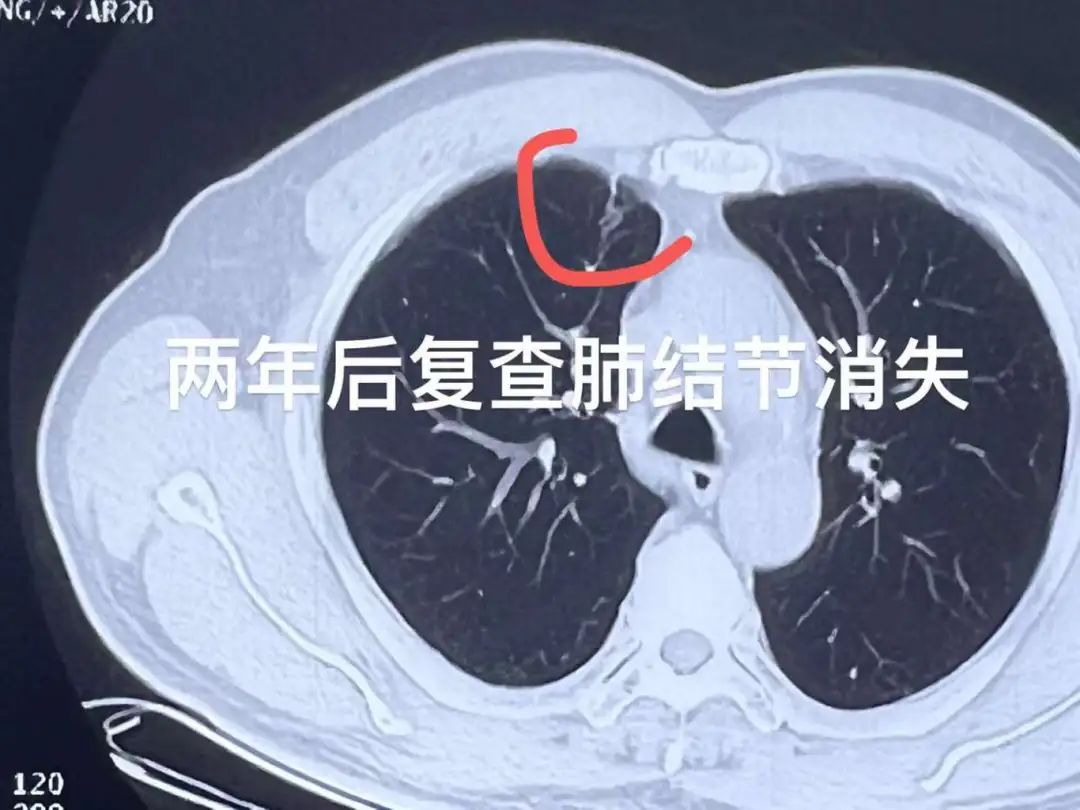

一大早,我办公室迎来一位患者。该患者两年前在我院接受了肺结节冷冻消融术,近期回院复查,发现两个肺结节已消失,在出院之际,患者很高兴地与我道别,还跟我说,他的“结友们”都在关注消融的效果,他就是消融效果的“榜样”。

作为国际冷冻治疗学会的主席单位、亚太肿瘤冷冻消融培训中心,广州复大肿瘤医院利用冷冻消融技术已治疗数十个癌种,在肺结节方面无论是治疗例数还是学术研究均位居前列。在2019年发布的《亚实性肺结节的冷冻消融》中,14名患者中的19个亚实性结节接受了冷冻消融,所有结节在24个月的中位随访期内均被完全消融,技术成功率为100%,无冷冻消融相关死亡病例。这一研究成功被国际权威专家共识引用。